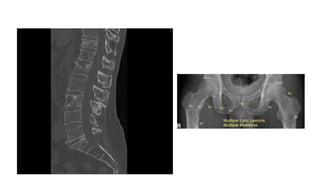

• PAIN

• Back or chest bone pain as result of vertebral or rib fractures at sites of

osteopenia or from lytic bone lesions is present at the time of diagnosis in

approximately 60 percent of patients.247 The pain is usually worse with

movement and at night. Pathologic fractures of long bones can ensue as well.